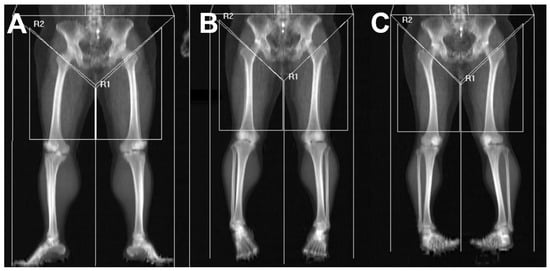

Thigh Segmentation and DEXA Acquisition

3.2. Influence of Lower-Limb Rotation on DEXA–CT Relationships